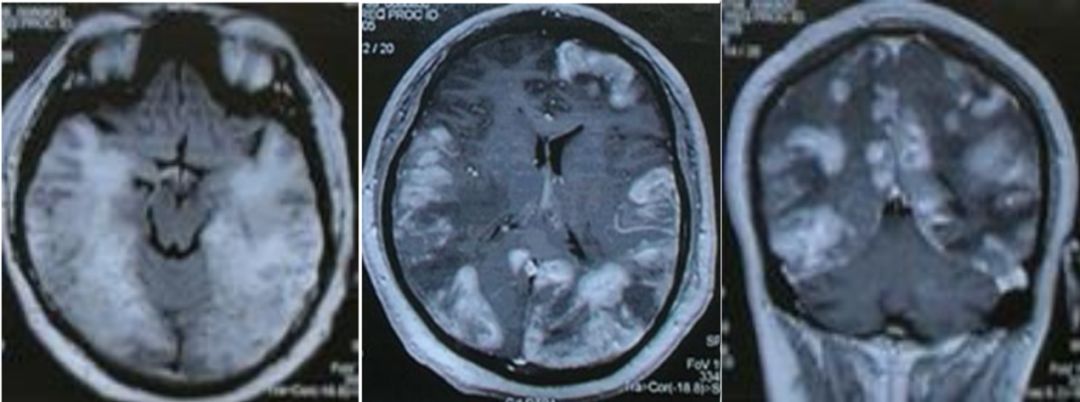

下面看图:

T2序列可见,双侧皮层下及深部白质高信号,融合成片。U形纤维亦有波及。

诊断: 苯中毒脑病。

影像学表现是较为典型的“葵花征”,大家看像吗?

苯中毒诱发的白质脑病在各地广泛存在而且比较常见,然而,缺乏特异性临床表现及实验室检查使其诊断困难。神经影像及有关病史常常是诊断中至关重要的。在本例中,甲苯中毒诱发的白质脑病患者出现恶化的认知损害, MRI T2加权像上呈现出向日葵样的特征性表现。甲苯吸入所致中枢神经系统损害是中毒诱发白质脑病中常见的来源之一。报道的症状多不具特异性,如头痛,头晕,认知损害。在没有造血系统损害的情况下,甲苯中毒性白质脑病可能不易诊断。